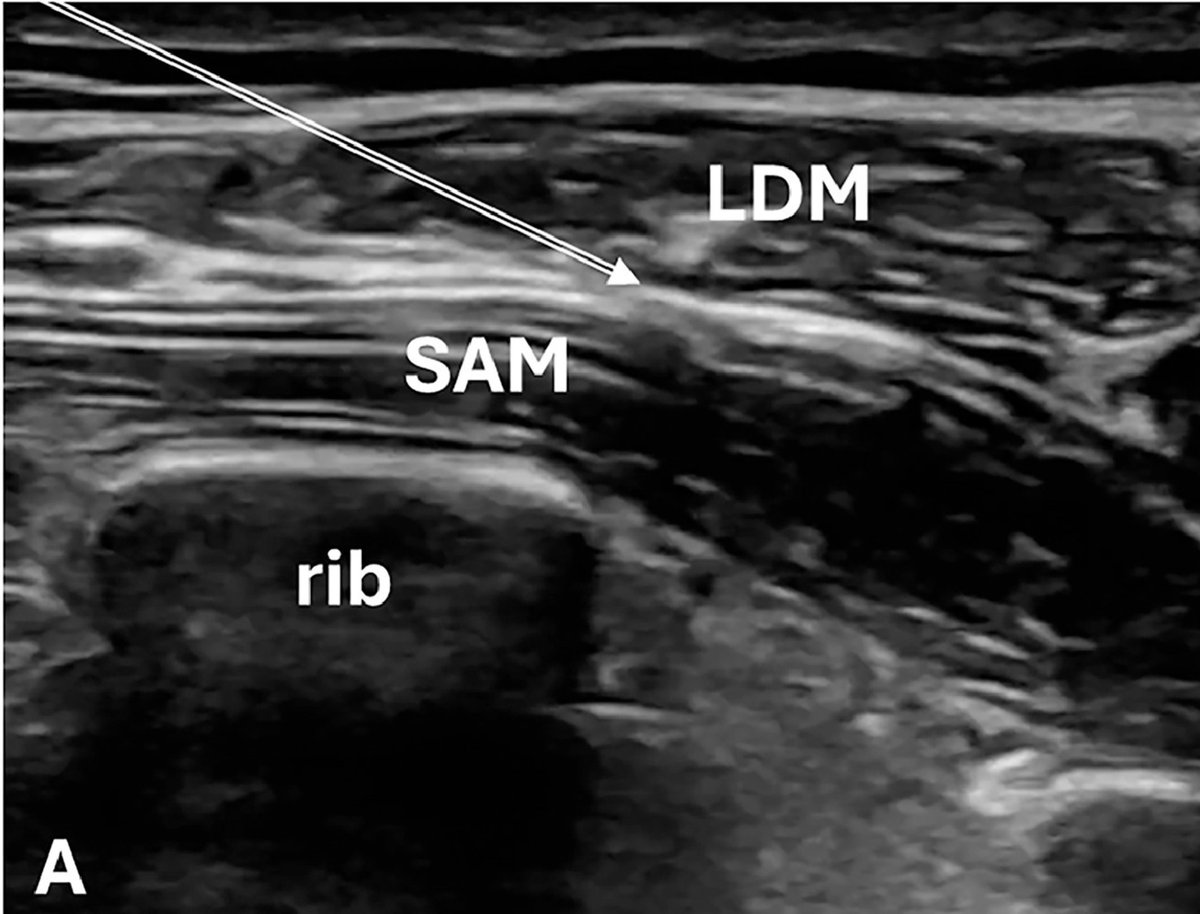

JEM Case of the Week Answer: Pain from Zoster? How about a #POCUS guided Serratus Anterior Plane Block! Check out the full case here. Penn EM Residency AAEM #medtwitter jem-journal.com/article/S0736-…

JEM Case of the Week Answer: Pain from Zoster?  How about a #POCUS guided Serratus Anterior Plane Block!  Check out the full case here. <a href="/UPennEM/">Penn EM Residency</a> <a href="/aaeminfo/">AAEM</a>  #medtwitter jem-journal.com/article/S0736-…

Thanks JEM_Journal! SAPB for severe zoster pain in a heart transplant patient…done safely in the ED. Immunosuppression isn’t always a contraindication. Check out our recent paper ⬇️ Penn Ultrasound Penn Medicine

Thanks #JournalFeed for featuring our recent review article published in JEM_Journal on the use of the Serratus Anterior Plane Block for managing acute chest wall pain in the ED! Penn Ultrasound Penn EM Residency jeff kramer journalfeed.org/article-a-day/…